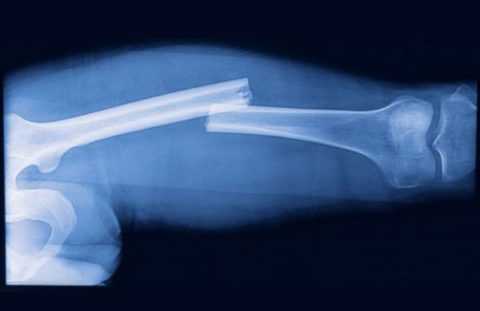

Наиболее опасен и в то же время достаточно распространен перелом шейки бедра. Лечение подобных поражений существенно осложняется сбоями процессов регенерации.

Стоит учитывать, что при продолжительном течении СД подобные показатели могут быть критическими, потому любая травма может оканчиваться переломом. В большинстве случаях под ударом оказываются ноги и тазобедренный сустав. Процесс срастания в обеих случаях довольно продолжительный.

Даже при неосложненном переломе процесс полного восстановления занимает достаточный отрезок времени. С наиболее выраженными сложностями сталкиваются медики в лечении переломов тазобедренного сустава или лодыжки. Такие переломы требуют оперативного вмешательства. Лечение чаще всего проходит в условиях стационара.